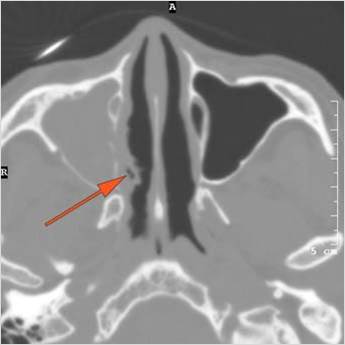

Nasal Cavity and Nasolacrimal Canal and Sac

There is  infiltration of the fat surrounding the nasolacrimal sac either preseptal or postseptal.

There is soft tissue infiltration or bone erosion along the nasolacrimal fossa or canal